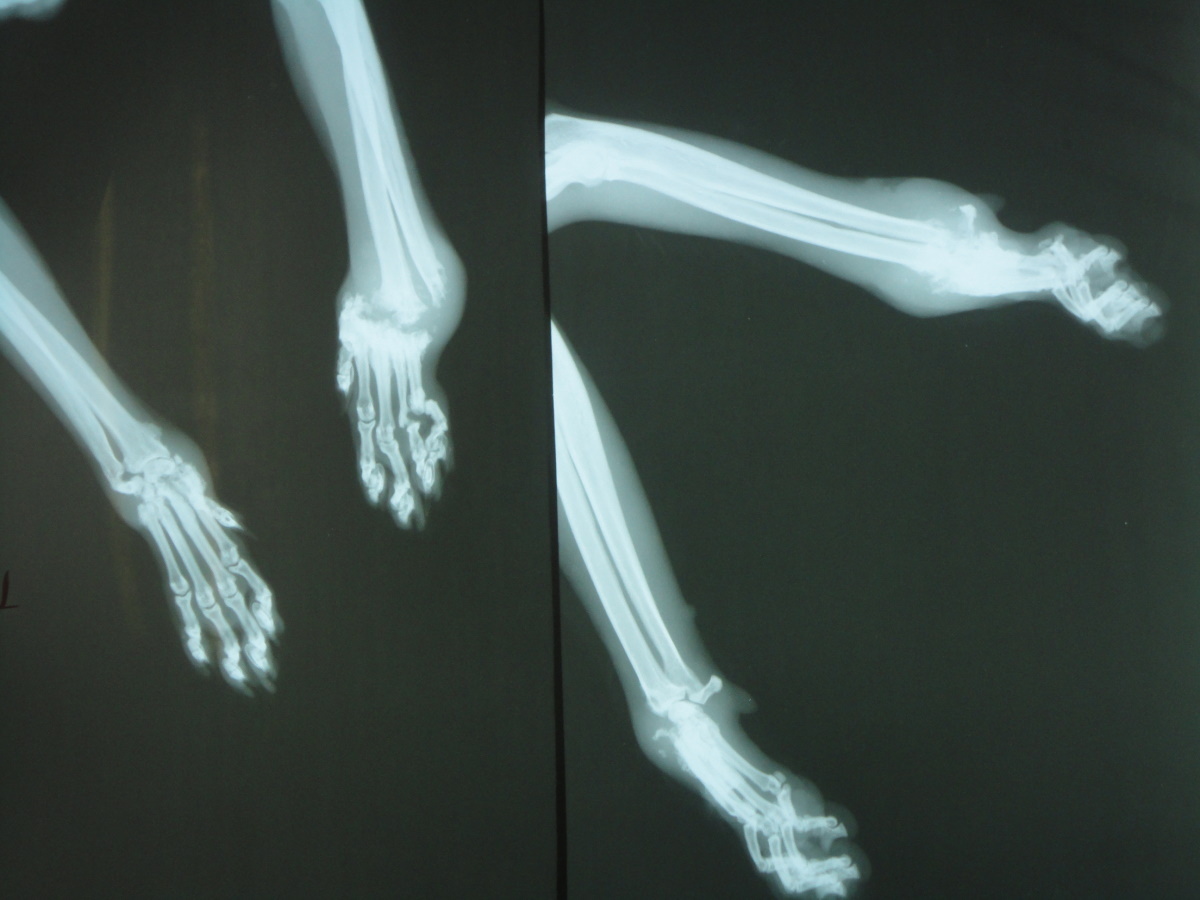

經聯絡由志工張先生協助,在兩天後捕捉,送醫檢查發現前肢疑似骨折,前肢x光片顯示左前肢腕骨已完全被蝕骨細胞破壞吸收,結構完全破壞,評估可能無法保留,右前肢部份趾骨及腕骨亦因骨折而遭破壞, 但大致結構仍完整,為了日後貓咪的生活品質著想,我們以保住貓咪雙腳為努力的目標,經過四個月漫長的醫療,貓咪的腳得以保存,雖然不會像正常貓那樣靈活,但行動自如,也由附近愛心人士照顧中,很感謝醫師大力幫忙,在醫療費用上給予極大的優惠。